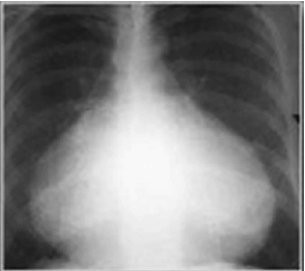

Uma adolescente de 12 anos foi levada à Emergência e sua mãe relata falta de apetite, mal-estar, náuseas e dor no peito, com irradiação para ombro esquerdo há 24 horas. A anamnese revela que foi submetida à correção cirúrgica comunicação intra-atrial (CIA) há 20 dias. O exame físico apresentou estado geral regular, t.ax: 382C; FR: 52 irpm; FC:100 bpm; PA: 100 x 60 mmHg; ACV: presença de discreto som de atrito pericárdico; AR: sem alterações; fígado e baço não palpados. Os exames laboratoriais apresentaram o seguinte resultado: HM: 4.800.00 mm³; Hb: 12,5 g/dL; Hto: 37,5%; Leucócitos 10.100/ mm³; B: 3%; S: 32%; L: 48%; VHS: 10 mm; RX de tórax. De acordo com o exposto, analise a imagem a seguir.

Assinale a alternativa que apresenta o diagnóstico e a conduta correta para o caso referido.